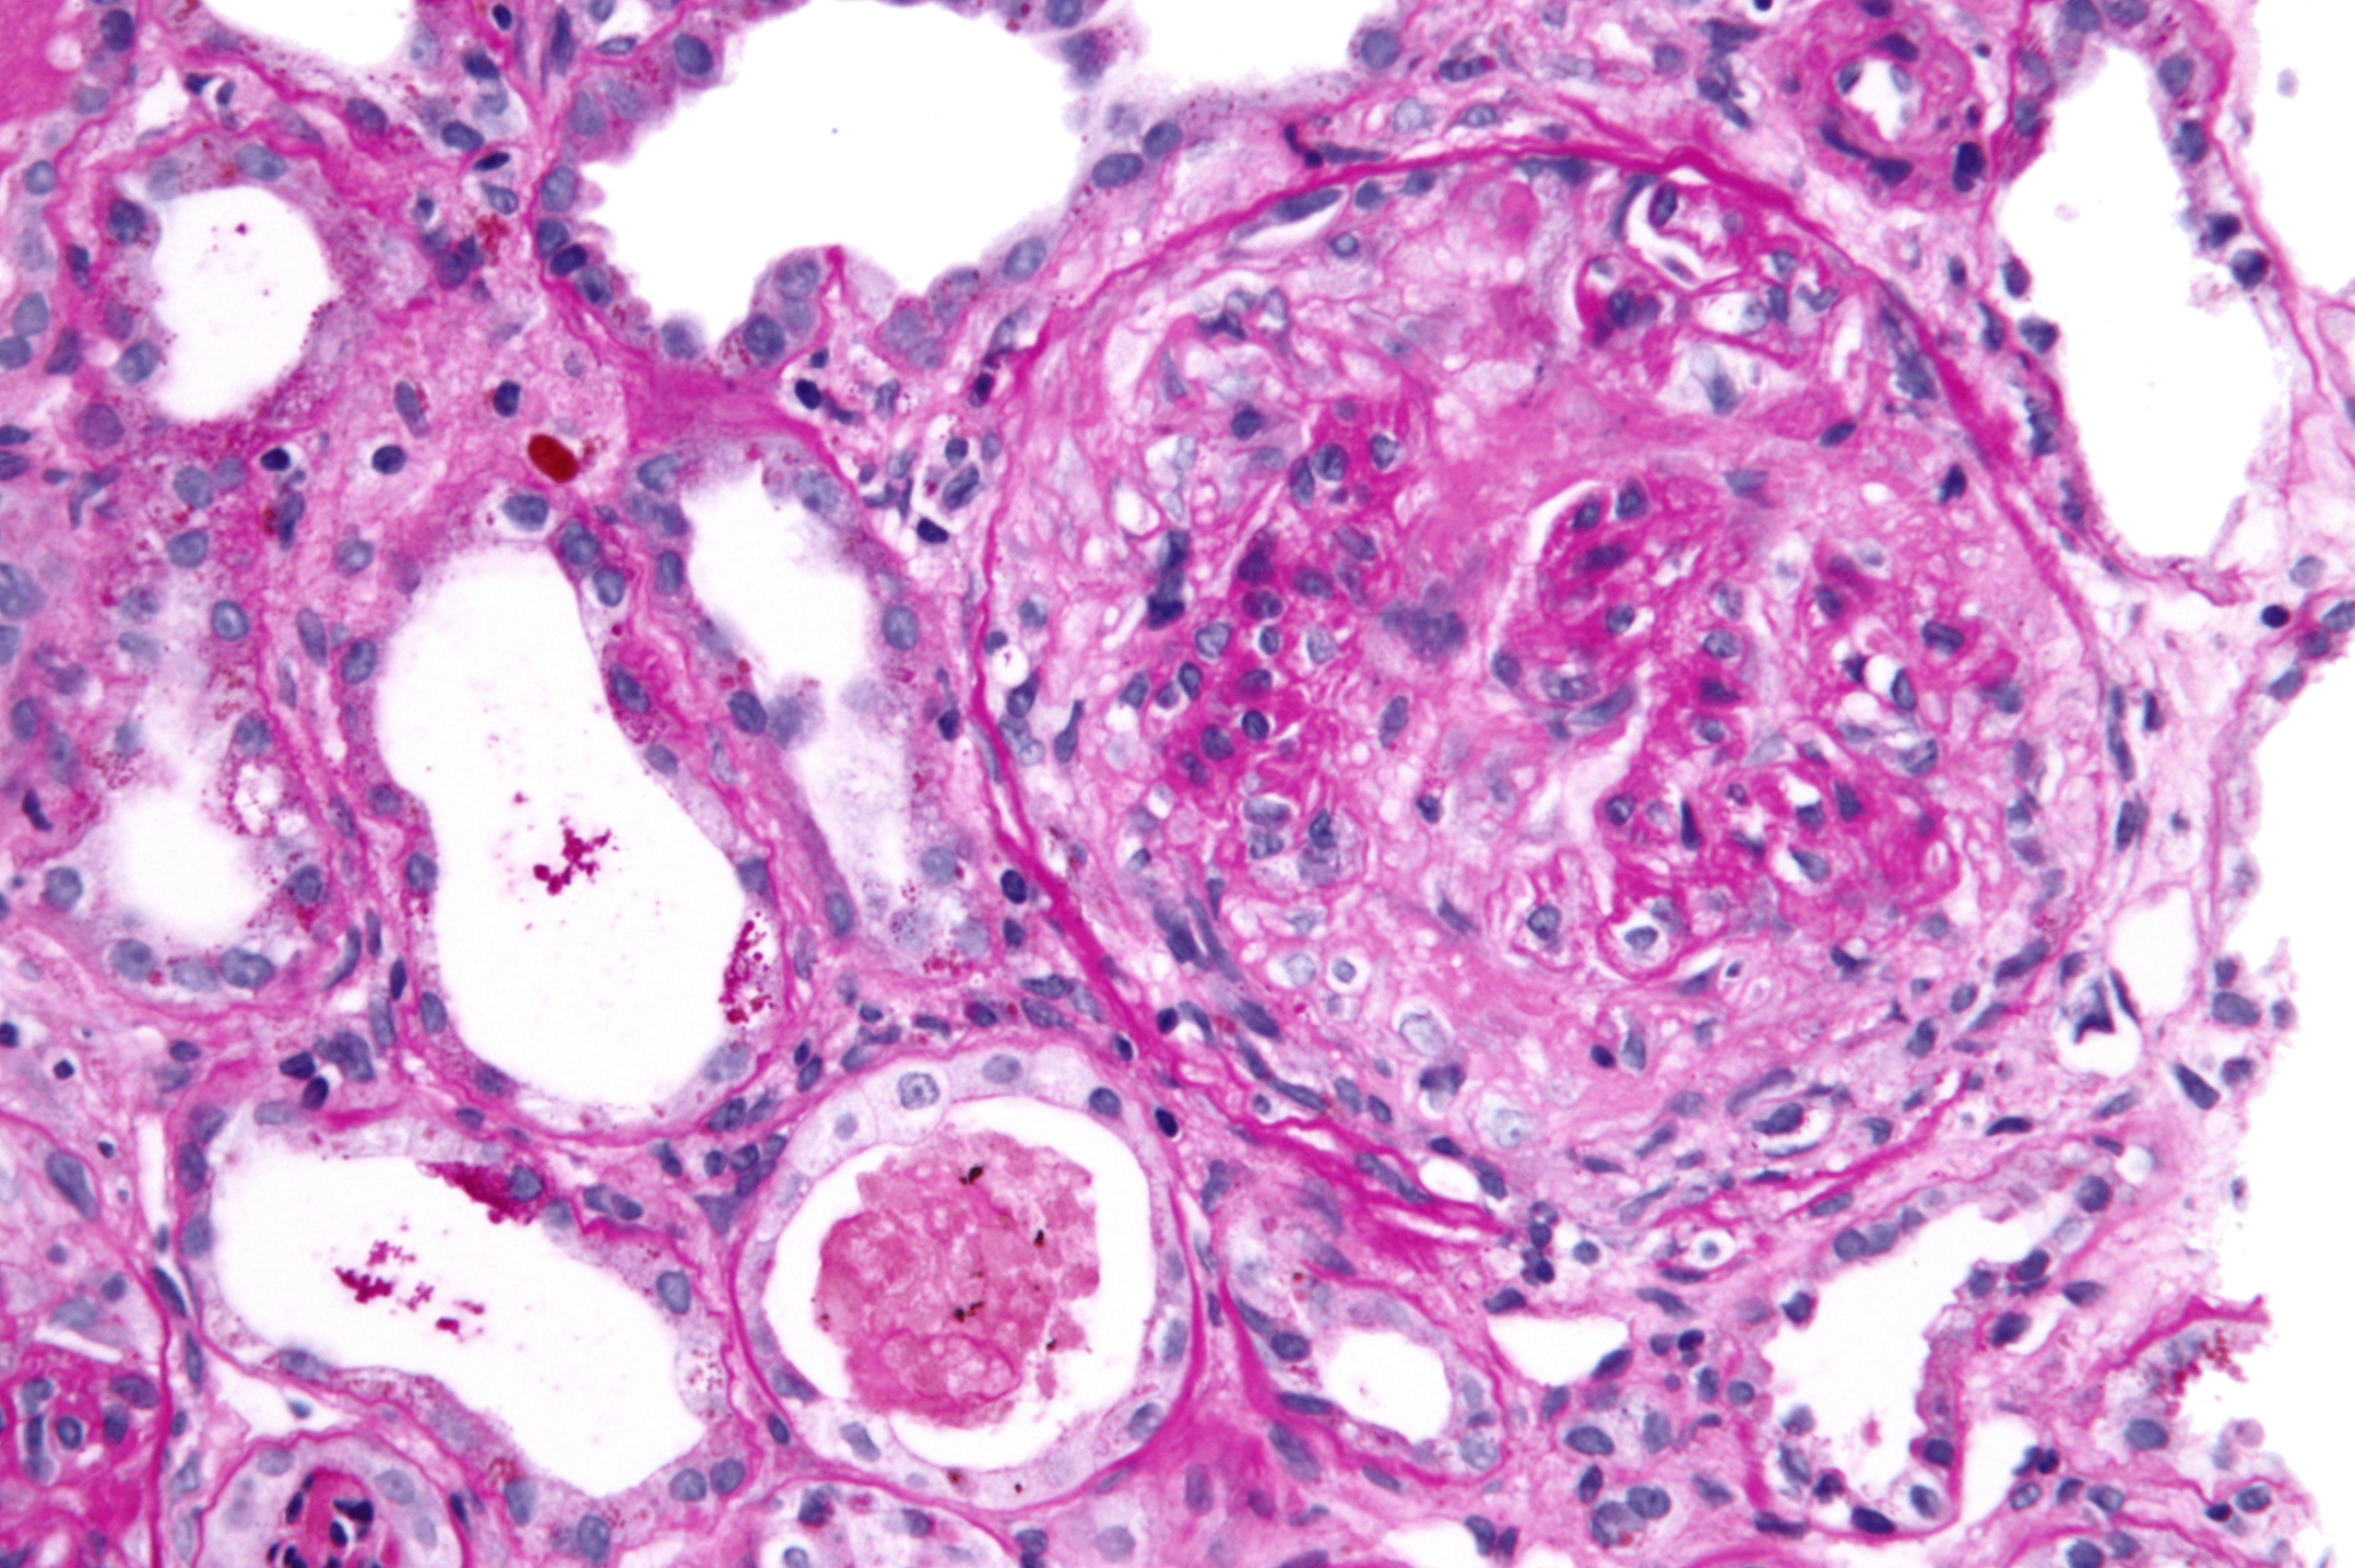

① 광학현미경

diffuse endocapillary proliferation

• 백혈구(주로 호중구) 침윤

사구체가 크고 과세포성(hypercellularity)을 보임

Postinfectious glomerulonephritis, Wikimedia Commons